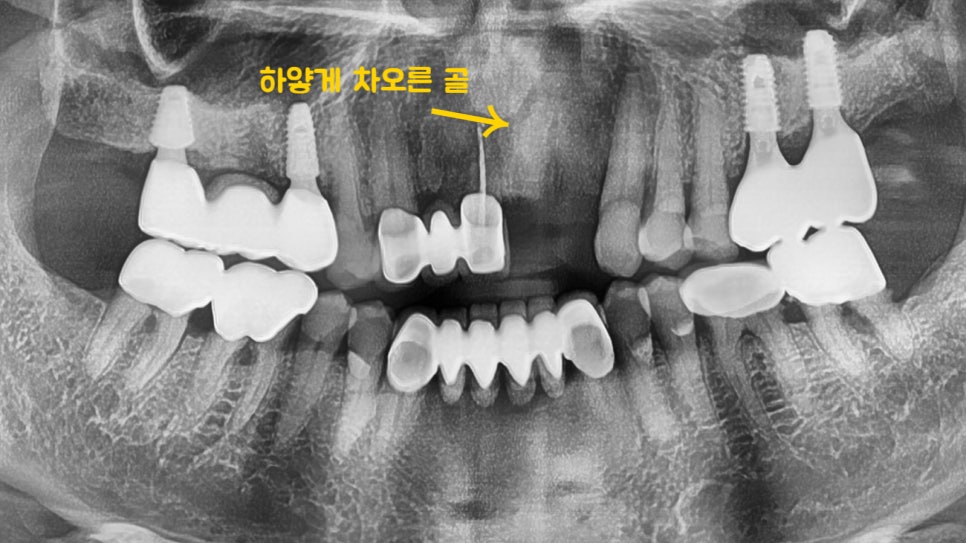

5개월 뒤,

치아가 없는 부위가 빵빵해지면서

골이식이 된 것이 확인이 되네요~

픽스쳐 식립까지 문제 없이 마무리 되었습니다.

이후 앞니 임플란트 의 최종 단계인

크라운 제작 만을 남겨둔 상황입니다.